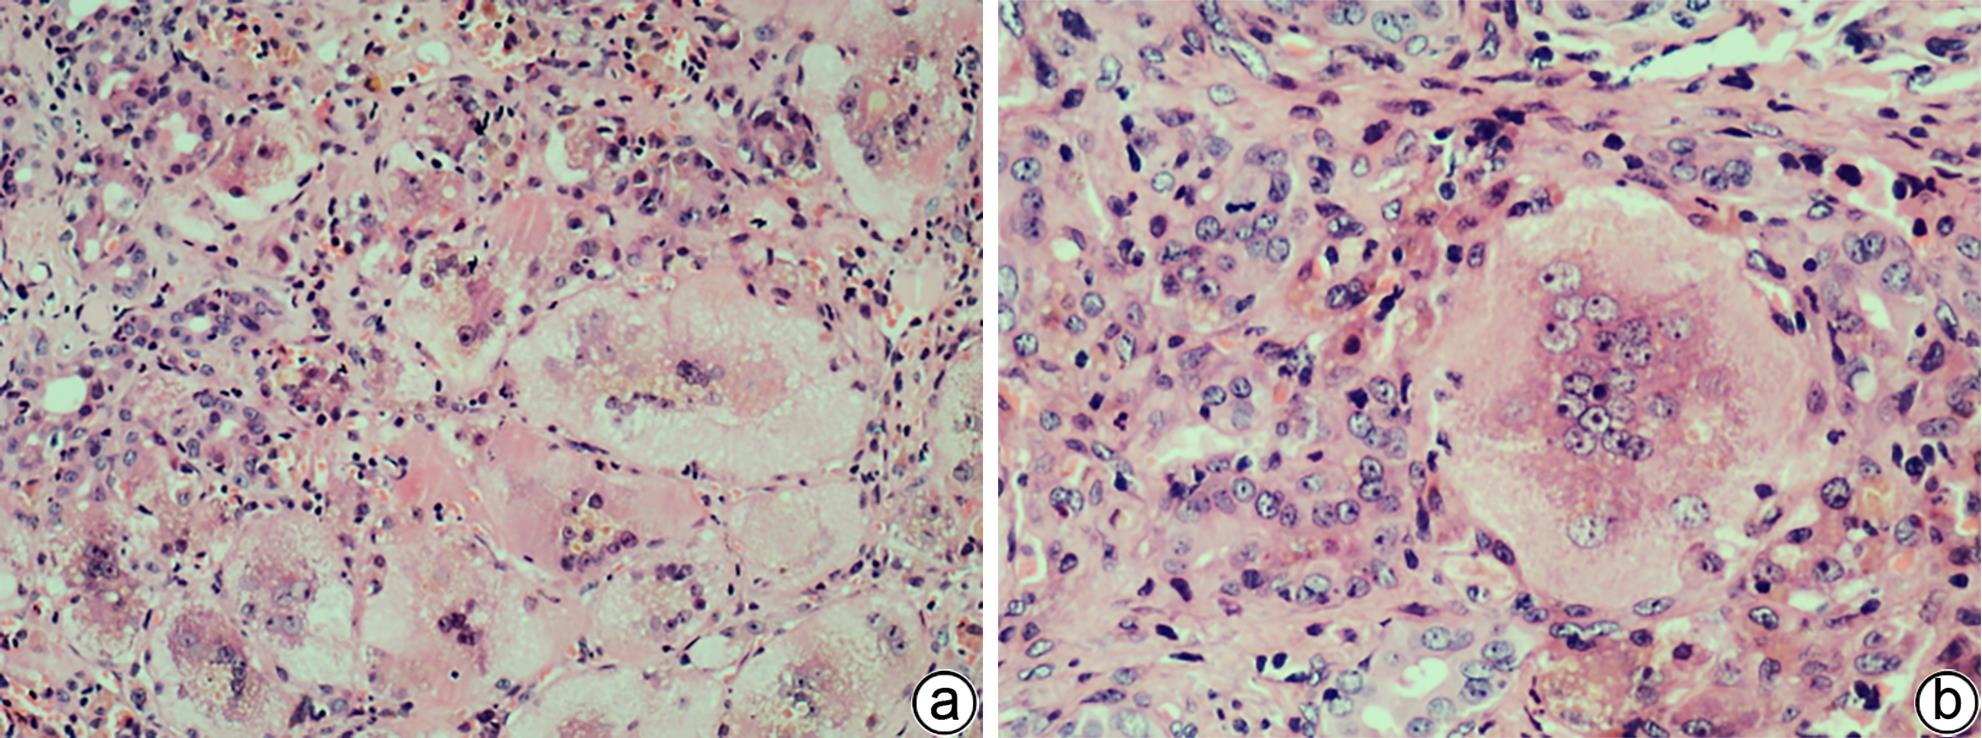

Autoimmune pancreatitis (AIP) is a rare disease, and its diagnosis should be made based on a comprehensive evaluation of clinical, radiological, serological, and pathological findings. At present, AIP is classified into two subtypes of type 1 (identified as the pancreatic manifestation of IgG4-related disease) and type 2 (identified as the pancreas-specific disorder independent of IgG4). Although type 1 and type 2 AIP seem to have different pathogeneses, they tend to have similar radiological findings and exhibit a good response to corticosteroid therapy. This article mainly reviews the histopathological features of the two subtypes of AIP, especially the diagnostic challenges encountered in the interpretation of specimens obtained through endoscopic ultrasound-guided fine needle aspiration/biopsy, to as to help pathologists enhance the accuracy of the diagnosis of AIP.